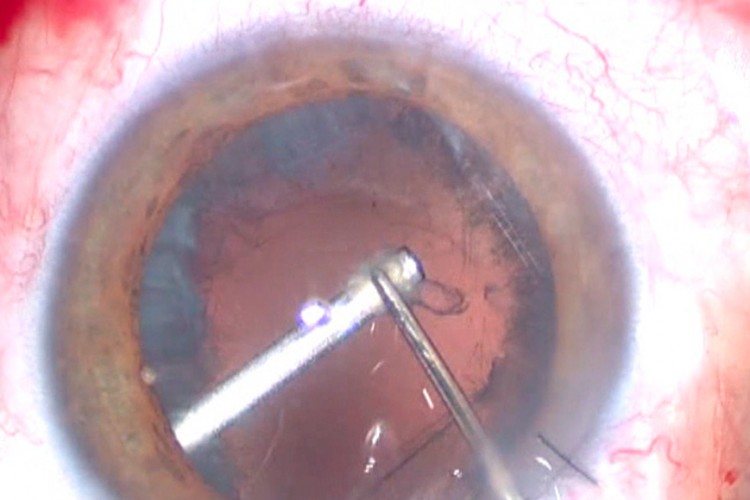

Greffe cornée Carlevale

Publié le 03 déc. 2025 par Sébastien Guigou